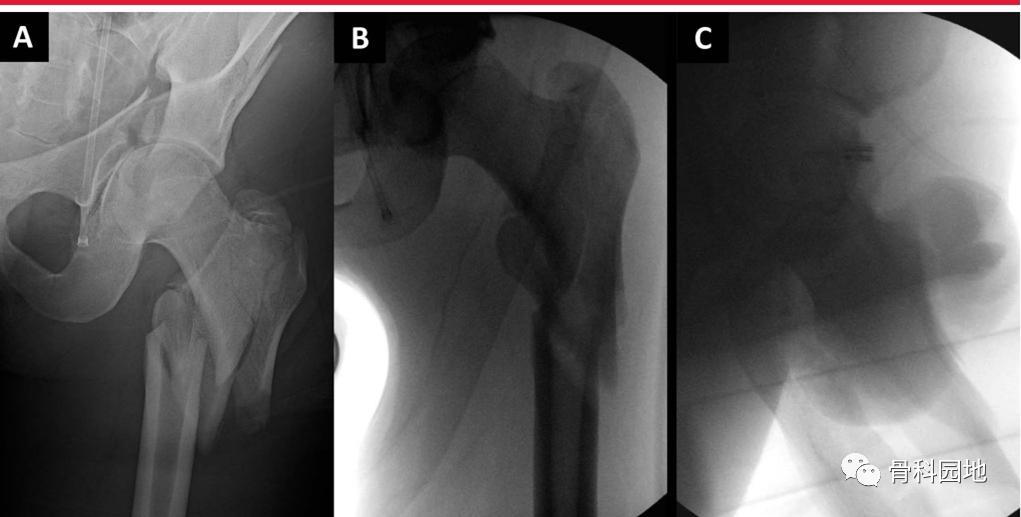

逆转子间骨折在复位和植入方面存在特别的挑战。需区分高能和低能粗隆部骨折,因为这些骨折的“表现”不同(下图)。虽然低能骨折可以在骨折手术台上通过闭合复位成功治疗,但高能骨折通常需要经皮或开放复位技术。

左侧髋关节侧位透视图显示尽管骨折手术台上有足够的牵引和旋转,骨折碎片仍有较大的移位。